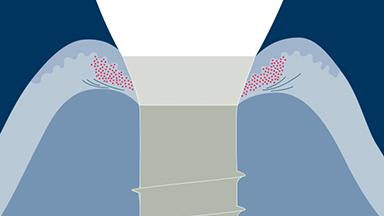

A substituição de dentes perdidos por meio de implantes endósseos tem provado ser uma modalidade de tratamento bem-sucedida para pacientes total e parcialmente desdentados. Este conceito é baseado no fenômeno biológico da osseointegração. Para um bom resultado a longo prazo de uma reconstrução implantossuportada, os tecidos duros e moles precisam ser estáveis e fornecer um suporte adequado para a reconstrução protética. Existem vários fatores de risco que podem afetar as taxas de sucesso e sobrevivência. Um clínico que planeja uma terapia com implantes precisa conhecer os fatores de risco que contribuem para os diferentes tipos de complicações que podem ocorrer após o tratamento.

- identificar os diferentes tipos de complicações que podem estar envolvidas na terapia com implante

- identificar os fatores de risco para essas complicações